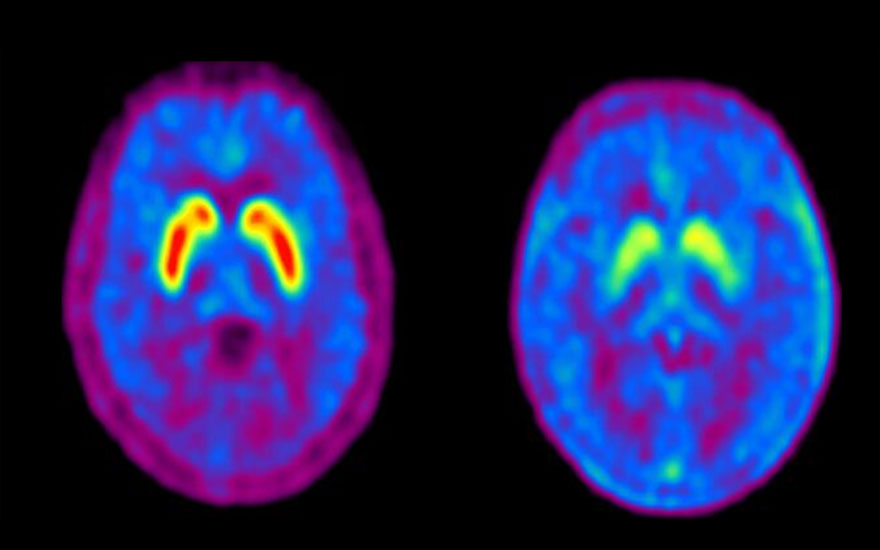

Izda. Paciente con captación normal de 18F-DOPA en los gánglios de la base. Dcha, paciente con poca captación (Parkinson).

La DOPA es un radiofármaco que se deposita en los ganglios de la base del cerebro. Una captación de DOPA normal indica que no se está desarrollando Parkinson. Si no se produce captación, se confirma la presencia de Parkinson.